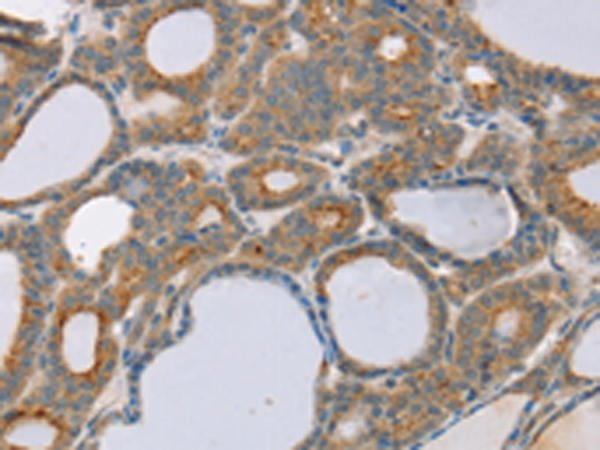

分类: 科研抗体货号: P05344别名: SBBI31; MSTP043应用: IHC反应种属: Human, Mouse